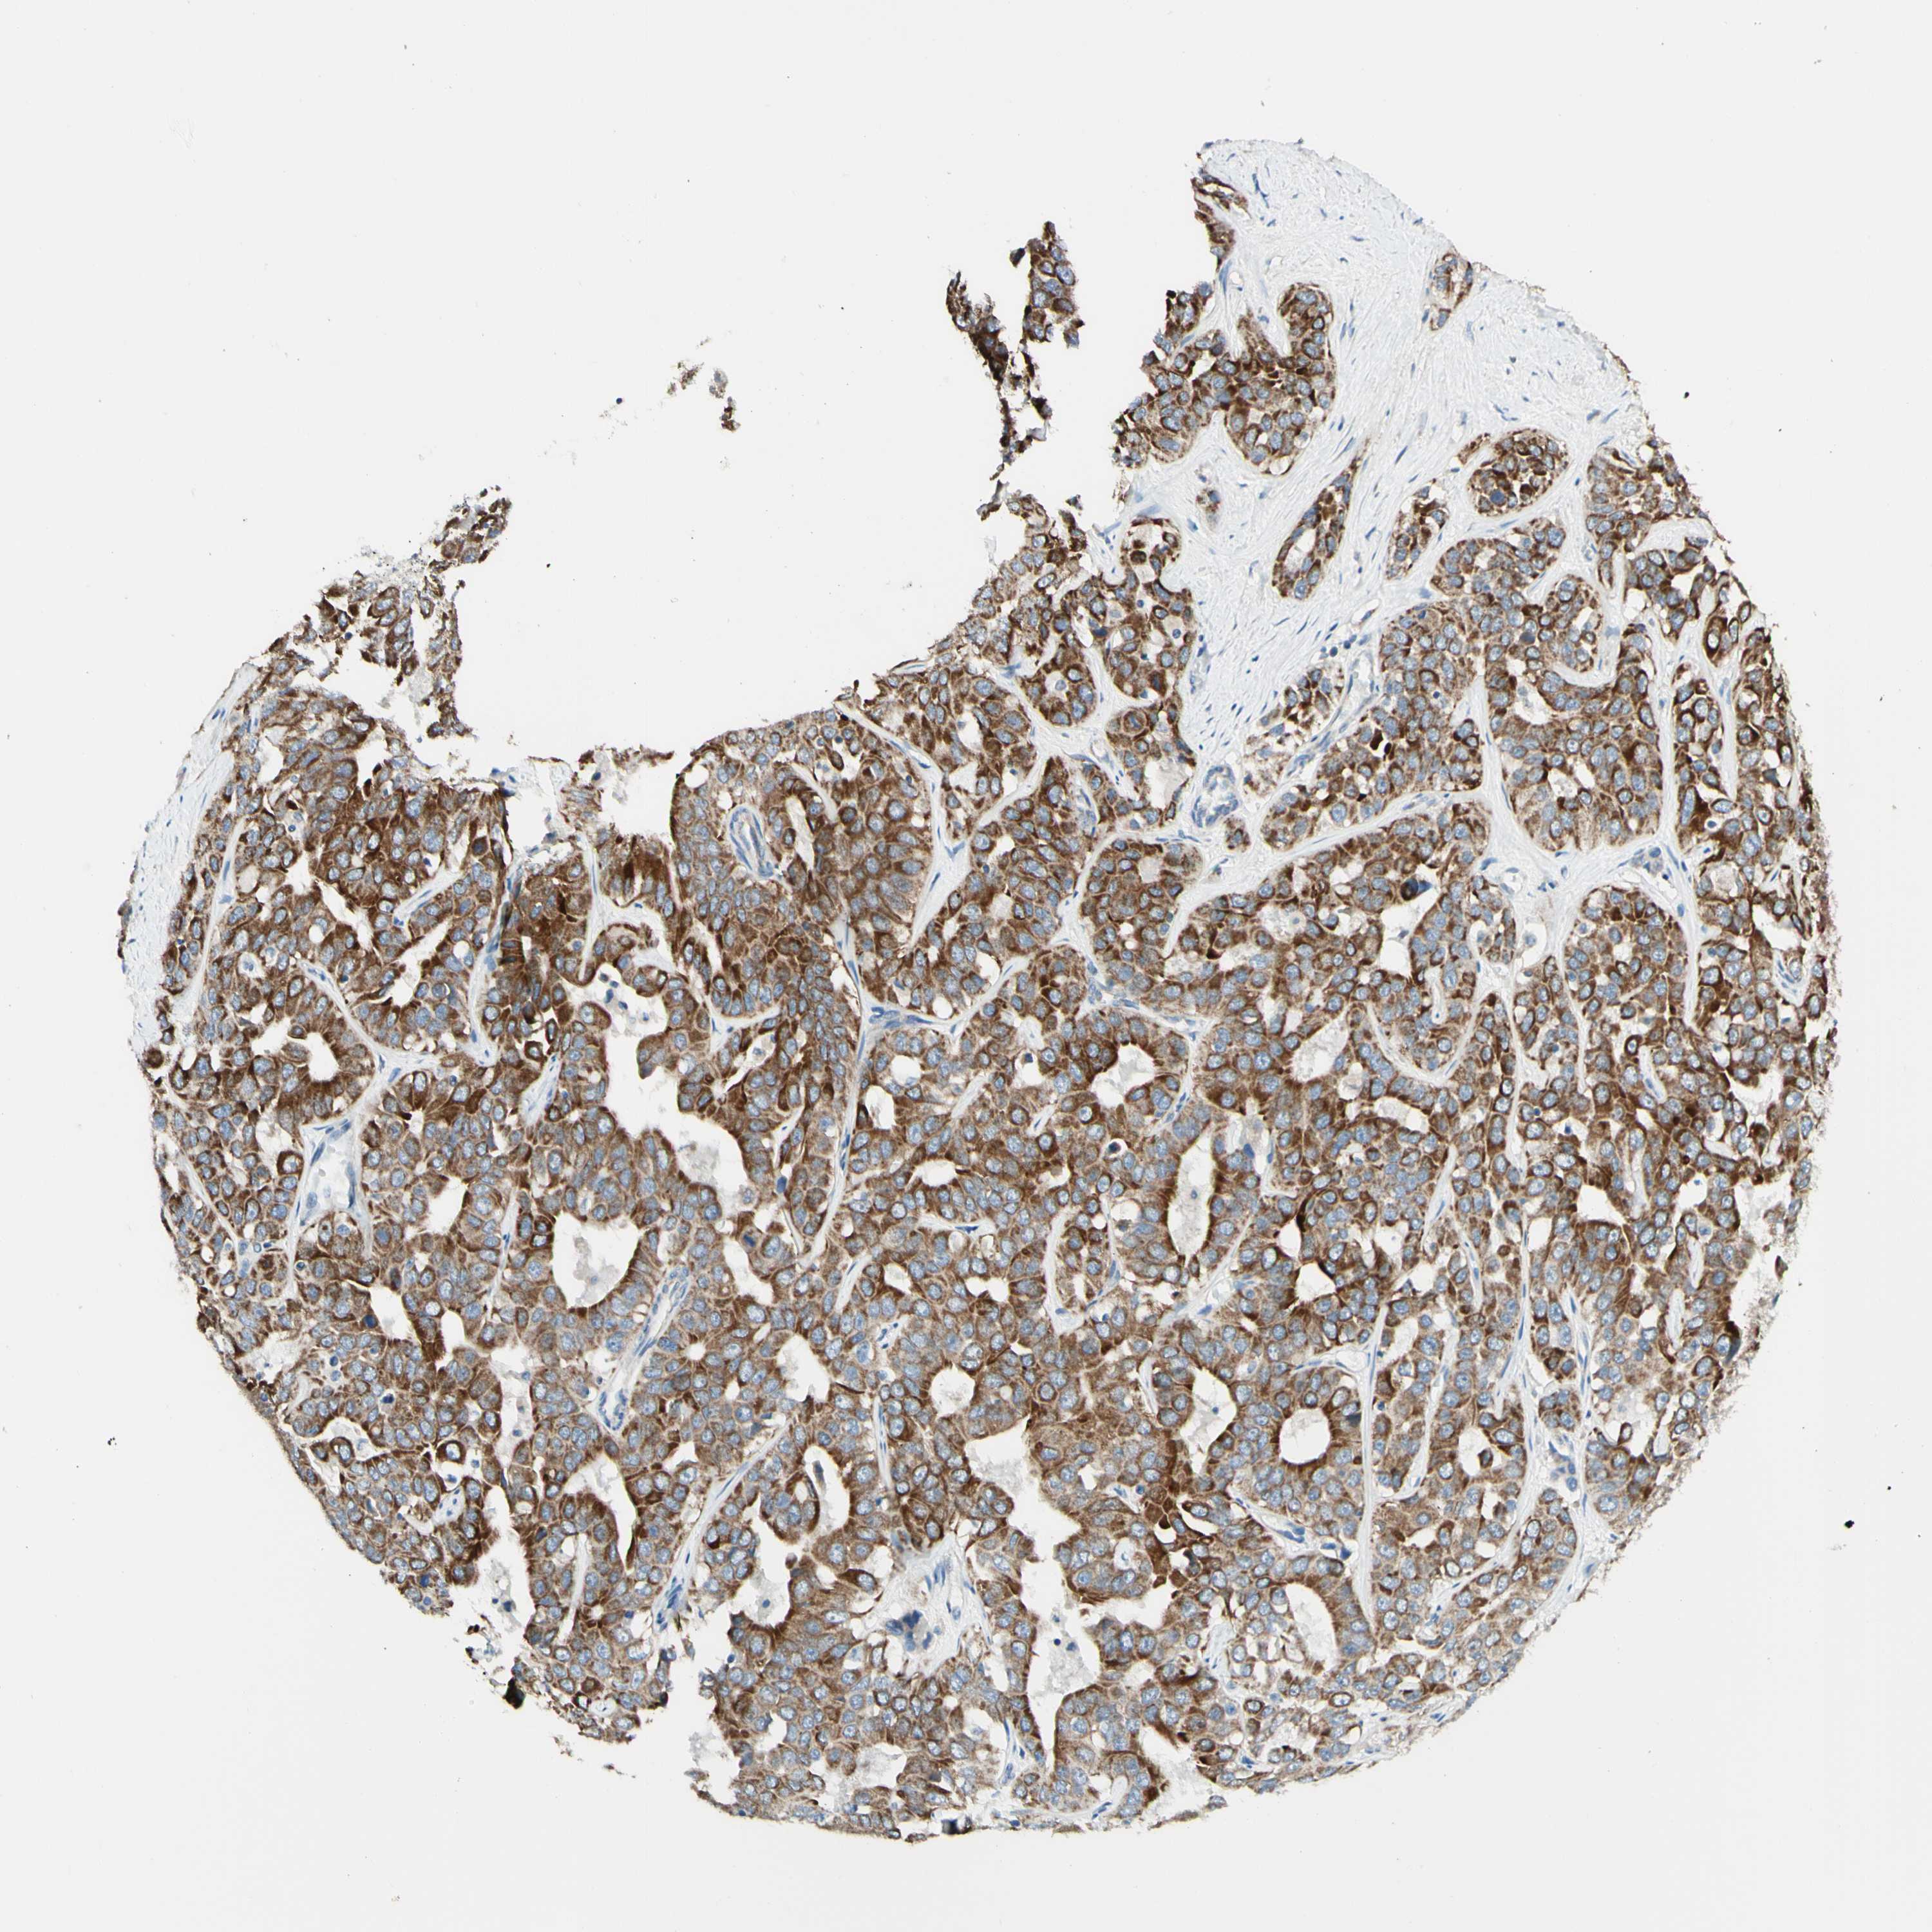

LIVER CANCER - Protein expressioni

A mouse-over function shows sample information and annotation data. Click on an image to view it in a full screen mode. Samples can be filtered based on level of antibody staining by selecting one or several of the following categories: high, medium, low and not detected. The assay and annotation is described here.

Antibody stainingi

Antibody staining in the annotated cell types in the current human tissue is reported as not detected, low, medium, or high, based on conventional immunohistochemistry profiling in selected tissues. This score is based on the combination of the staining intensity and fraction of stained cells.

Each image is clickable and will lead to virtual microscopy that enables deeper exploration of all samples and also displays staining intensity scores, fraction scores and subcellular localization as well as patient and tissue information for each sample.

Antibody HPA011036

Antibody HPA011057

Staining

High

Medium

Low

Not detected

Intensity

Strong

Moderate

Weak

Negative

Quantity

>75%

75%-25%

<25%

None

Location

Nuclear

Cytoplasmic/membranous

Cytoplasmic/membranous,nuclear

Cholangiocarcinoma

Carcinoma, Hepatocellular, NOS